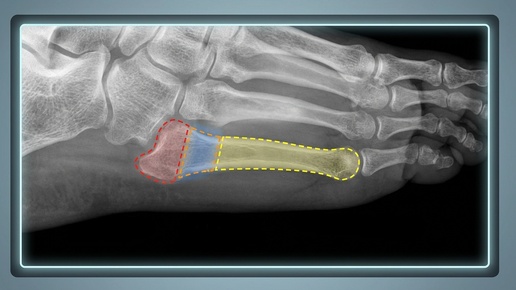

Переломы плюсневых костей

Плюсневые кости представляют собой длинные кости среднего отдела стопы. Их переломы распространены среди людей различных возрастных групп и видов физической активности. Травмы, связанные с этими костями, далеко не редкость в мире спорта. Чаще всего встречаются стресс-переломы или переломы, полученные в результате механического воздействия. Так, стресс-переломам плюсневых костей подвержены в основном бегуны, триатлонисты и ультрамарафонцы.

В обычной стопе человека 5 плюсневых костей, которые соответствуют пяти пальцам...